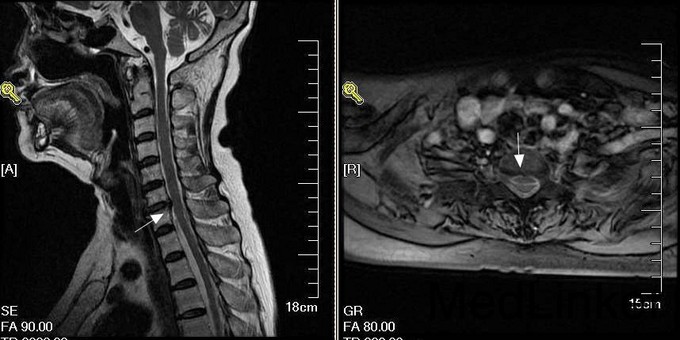

神经内科查体:神清、语明,面纹对称,伸舌居中,双上肢活动既感觉基本正常,平脐水平以下深浅感觉障碍,双下肢肌力0级,腱反射未引出,双侧巴氏征-,颈强+。患者存在感觉平面、截瘫及尿边障碍,根据患者临床表现考虑存在脊髓病变,遂急诊行颈段MRI检查,见图:

诊断:脊髓硬膜外出血 建议患者手术治疗,但患者家属要求转院治疗。

自发性脊髓硬膜外出血的发病机制目前不完全清楚,巴特森静脉丛损伤、术前高凝状态及抗凝治疗、肿瘤脊髓内的小血管瘤、未控制的高血压以及胸腹腔压力的突然升高等均有可能是发病原因。自发性脊髓硬膜外血肿常以突发颈部背部腰部疼痛为首发症状,进而出现神经根受压症状直至脊髓受压平面以下的运动感觉功能丧失。但是有些患者的症状会延迟出现,有一部分患者的症状会不典型。自发性脊髓硬膜外出血起病急,进展快,手术治疗是首选,特别是急性及亚急性期的出血,一经确诊排除手术禁忌证后应尽可能早期行血肿清除减压术。